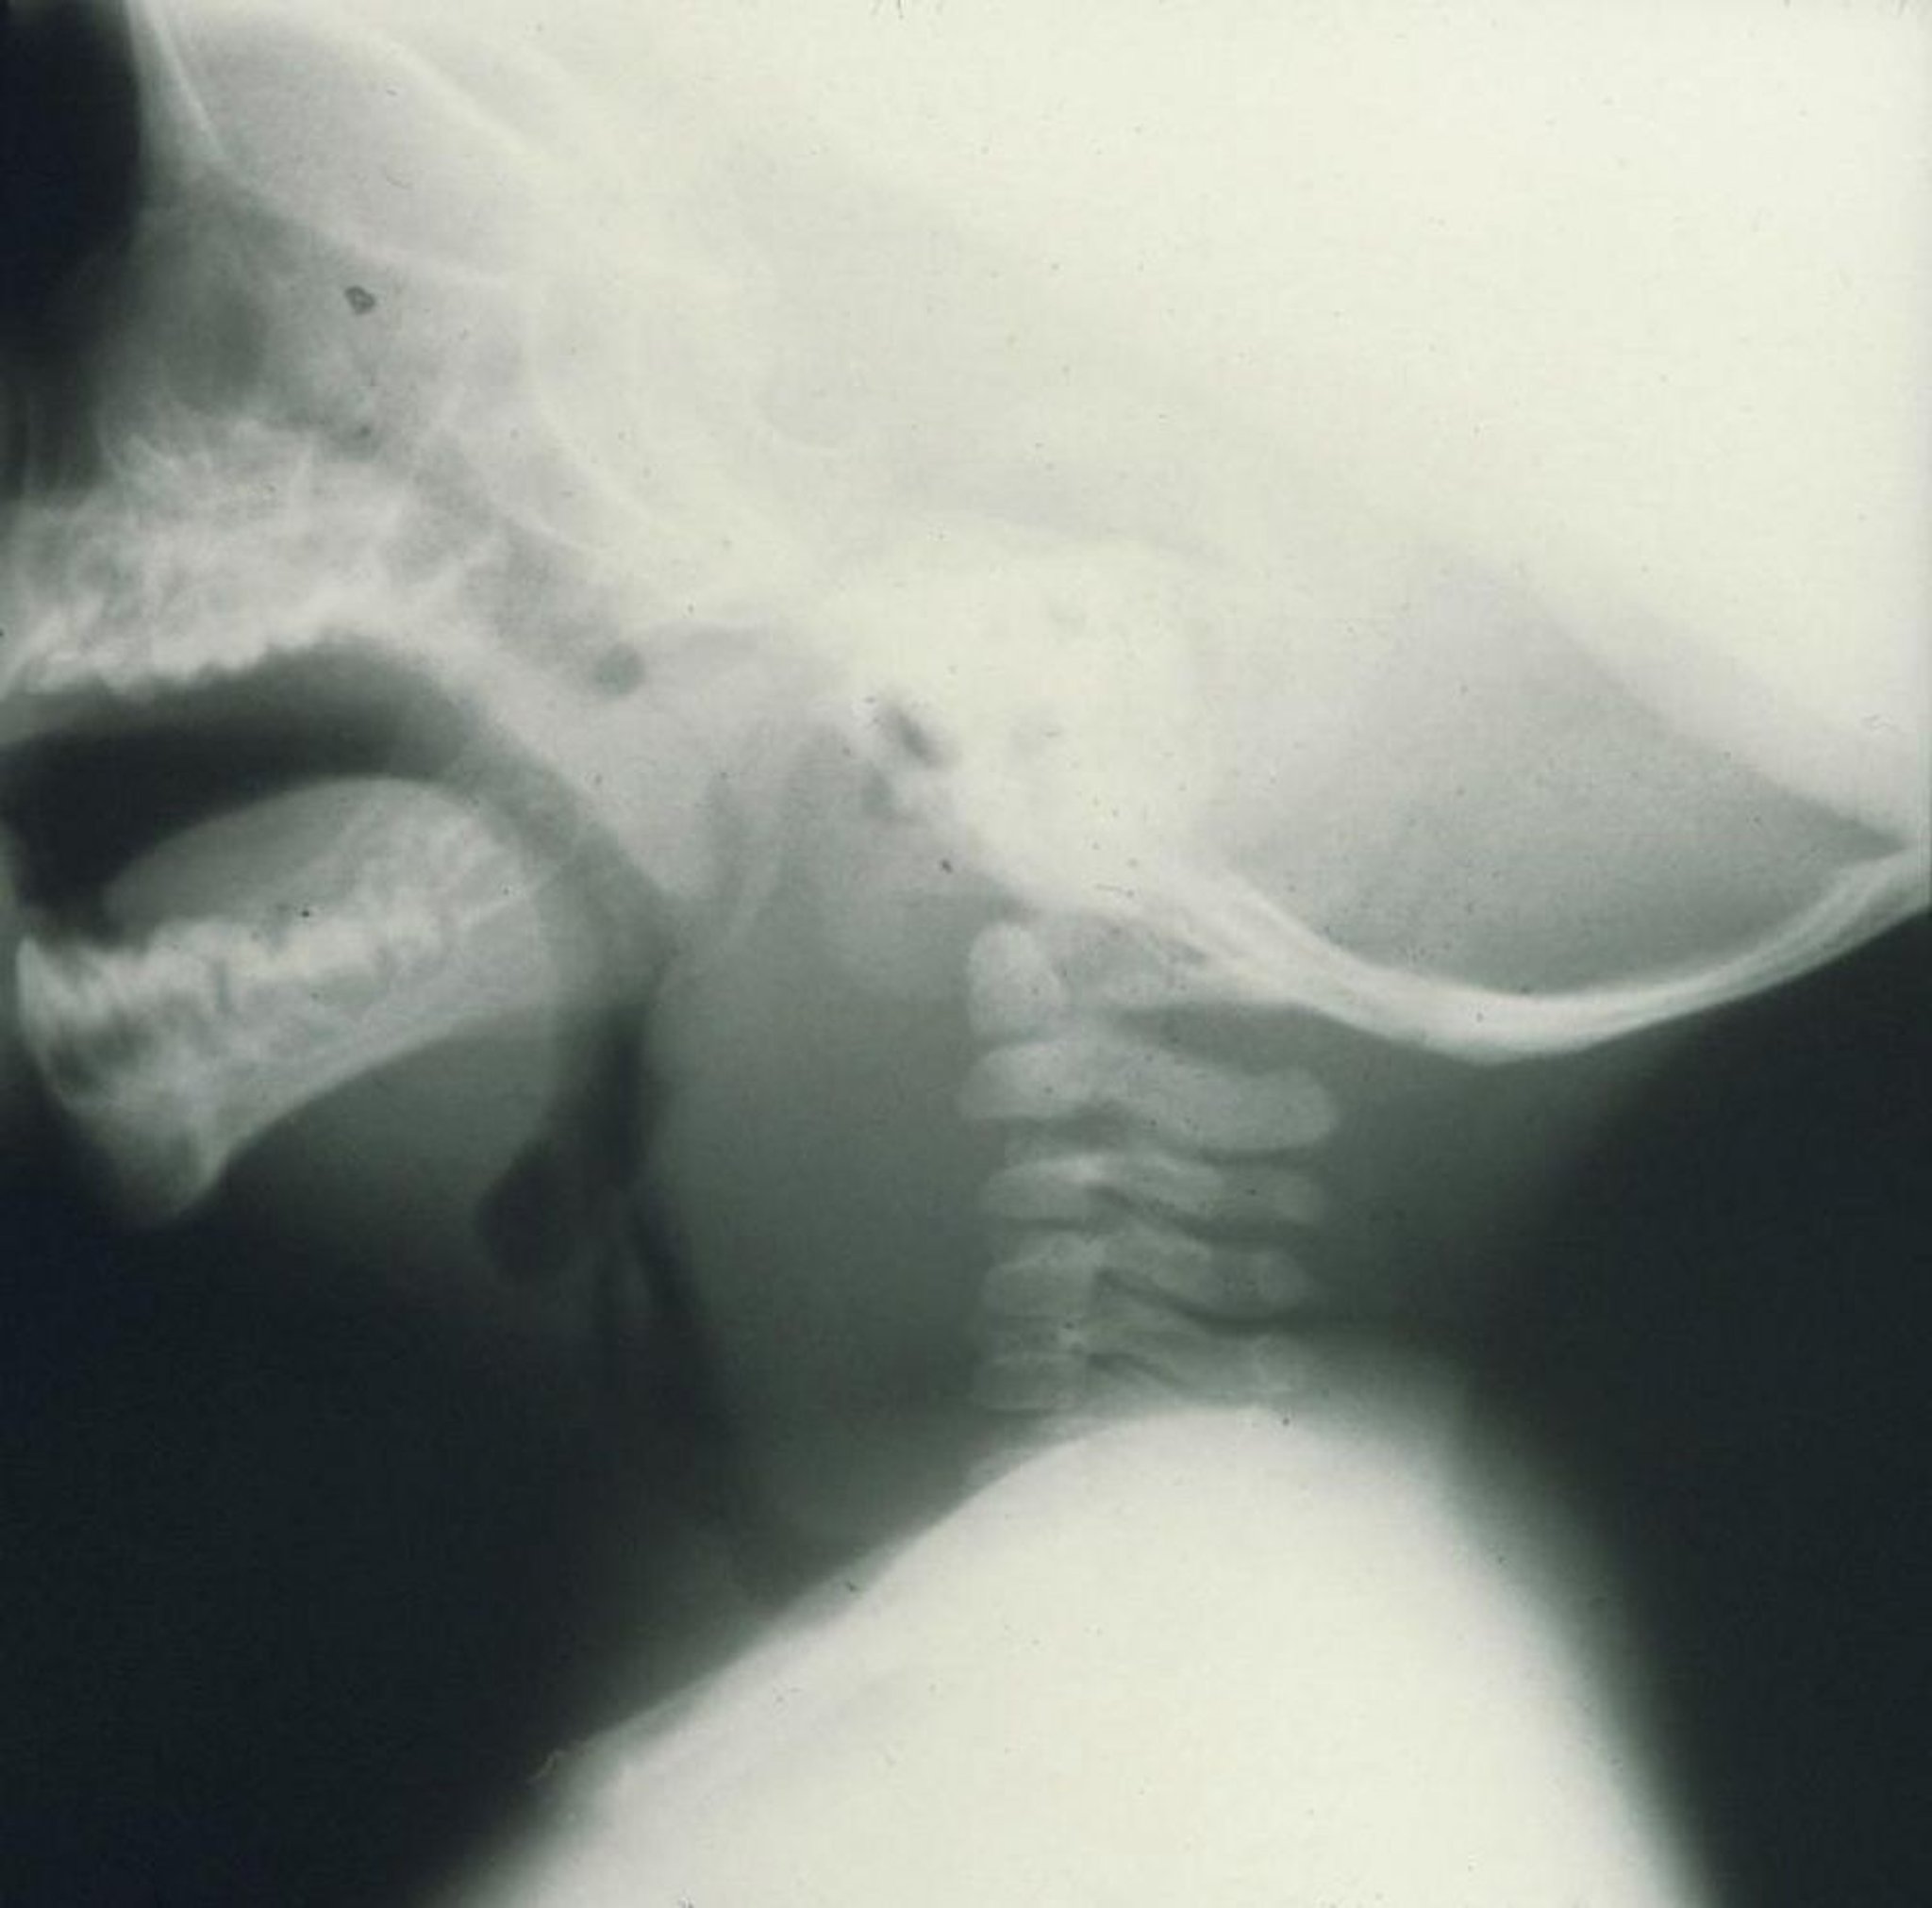

Áp xe sau họng

Ảnh chụp X-quang phim nghiêng này của một trẻ cho thấy sưng rõ trước đốt sống cổ do áp xe sau họng gây ra.

Hình ảnh do bác sĩ Clarence T. Sasaki cung cấp.